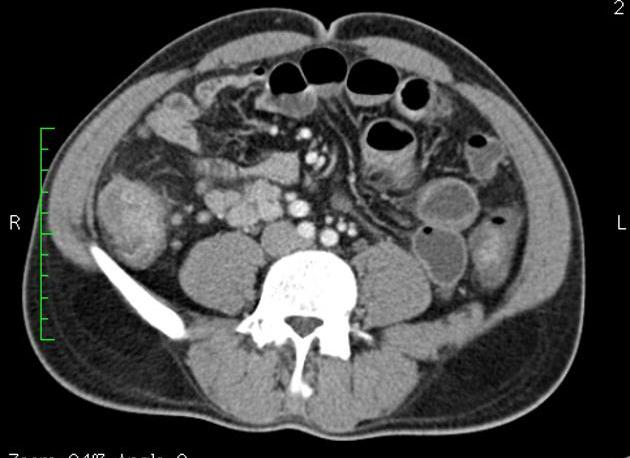

Aspect TDM du tuberculose ileocaecale est : Epaissisement

circumferentiel de la paroi ileum et caecum . Asymetrique

epaissisement de la valve ileocaecale .Mesenteric

lymphadenopathie et tuberculose pulmonaire est le plus

souvent .

Epaissisement hyper-densite

de la paroi de ileon . Image TDM en coupe axiale |

Tuberculose ileocaecale avec image de

deformation du caecum . Epaissisement asymetrique du

caecum avec image de lymphadenopathie

mesenterique . TDM en coupe axiale |